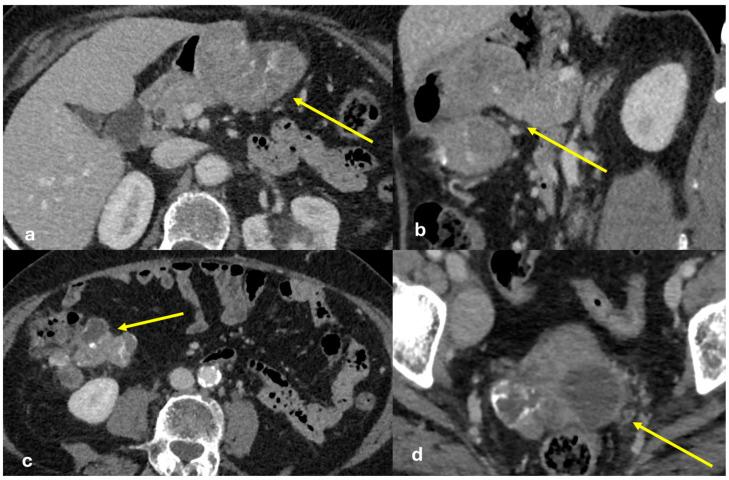

The peritoneum is a thin membrane that lines the abdominal cavity and covers the abdominal organs. It serves as a conduit for the spread of various pathological processes, including gas and fluid collections, inflammation, infections, and neoplastic conditions. Peritoneal carcinomatosis is the most common and well-known pathology involving the peritoneum, typically resulting from the dissemination of gastrointestinal and pelvic malignancies. However, numerous benign and malignant peritoneal diseases can mimic the imaging appearance of peritoneal carcinomatosis. The aim of this review is to revisit the anatomy of peritoneal compartments and elucidate the patterns of peritoneal disease spread. Emphasis is placed on identifying the distinctive imaging features of both neoplastic and non-neoplastic peritoneal diseases that differ from peritoneal carcinomatosis.

腹膜是一层薄的膜,它衬于腹腔内并覆盖腹部器官。它是各种病理过程扩散的通道,包括气体和液体聚集、炎症、感染及肿瘤性疾病。腹膜癌病是涉及腹膜的最常见且广为人知的病理情况,通常由胃肠道和盆腔恶性肿瘤的播散引起。然而,许多良性和恶性腹膜疾病可模仿腹膜癌病的影像学表现。本综述的目的是重新审视腹膜腔室的解剖结构并阐明腹膜疾病的扩散模式。重点在于识别与腹膜癌病不同的肿瘤性和非肿瘤性腹膜疾病的独特影像学特征。